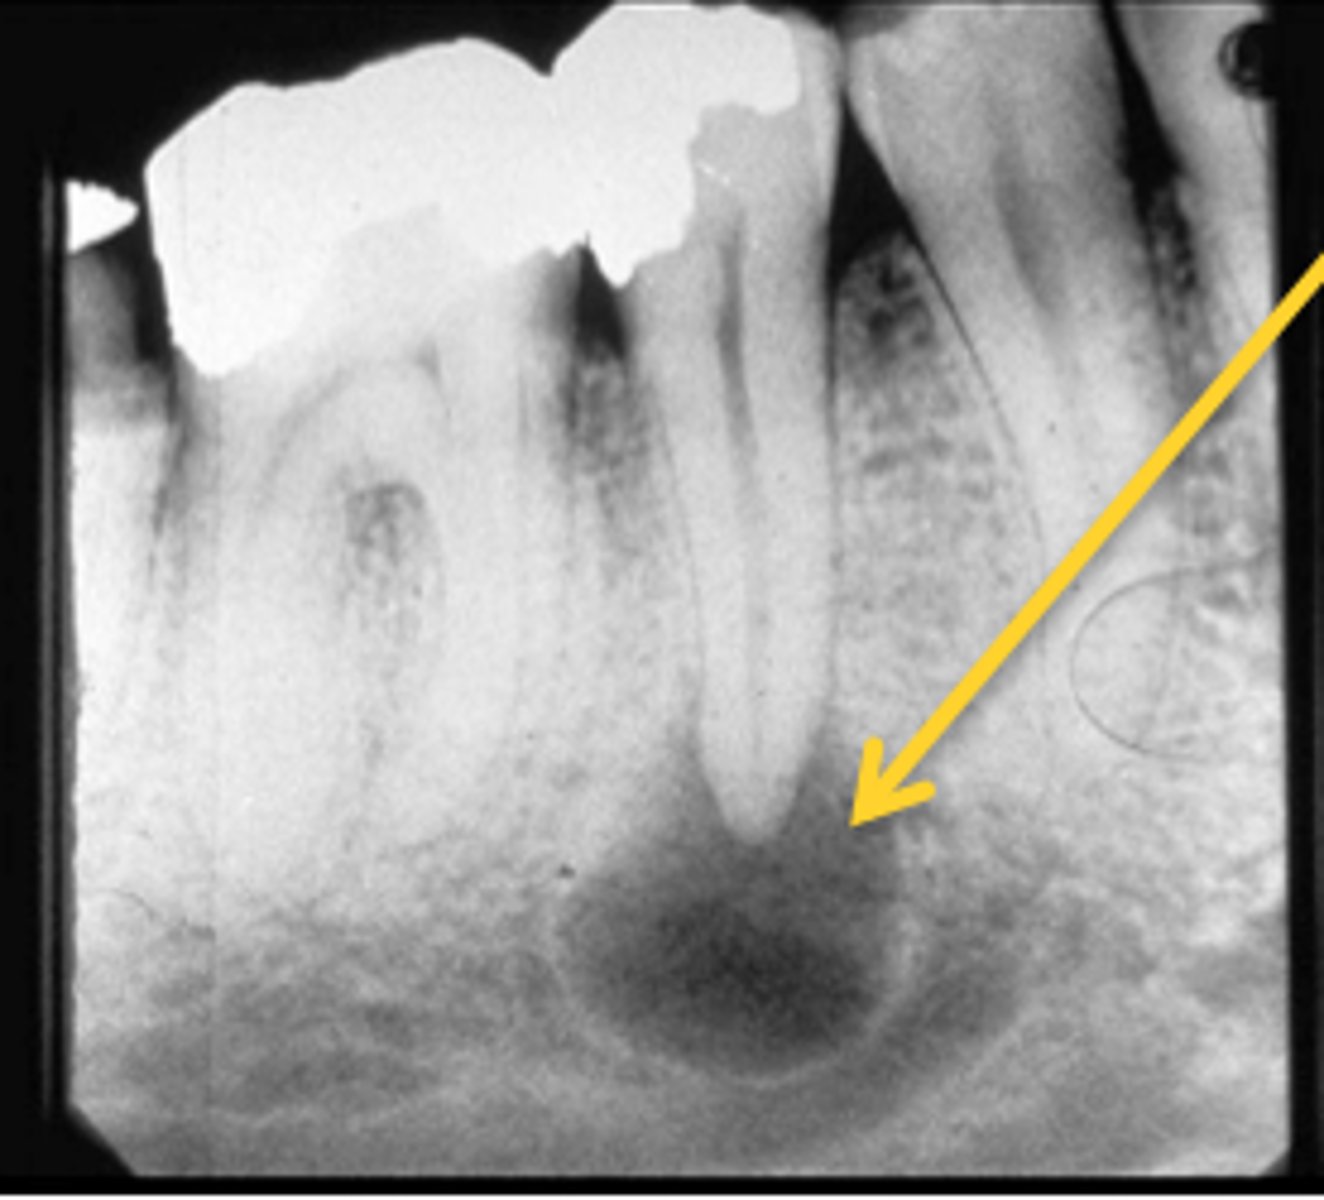

What area does odontogenic keratocyst (OKC) expand?

Mandibular posterior area

How does odontogenic keratocyst (OKC) expand around teeth?

Around entire tooth

What is the recurrence rate of odontogenic keratocyst (OKC)?

High recurrence rate

What are the differential diagnoses for odontogenic keratocyst (OKC)?

Ameloblastoma, dangerous cyst